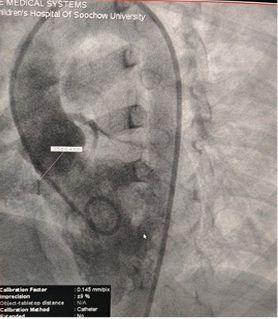

Successful Closure of Multi-Exit Membranous Septal Aneurysm-Type VSD Using MemoSorb Fully Biodegradable Occluder

Base diameter: ~6.1 mm with multiple exit points

Diagnosis: Perimembranous VSD

Selected MemoSorb ABFDQ-II 9 occluder based on intraoperative angiography and echocardiographic assessment.